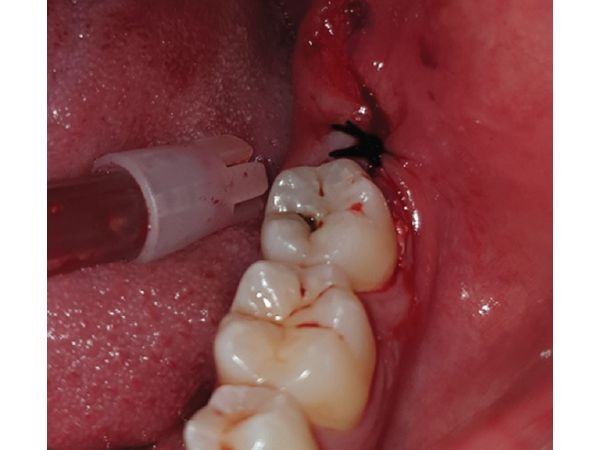

- Лунку промыли физиологическим раствором и скорректировали костные неровности. На лунку наложили швы нитью Викрил 6:0.

Через семь дней после удаления пациент пришёл на осмотр. Жалоб у него не было, рана заживала вторичным натяжением и без осложнений, динамика была положительной. В это же посещение сняли швы, лунку обработали физиологическим раствором (0,09%-м раствором Натрия хлорида).